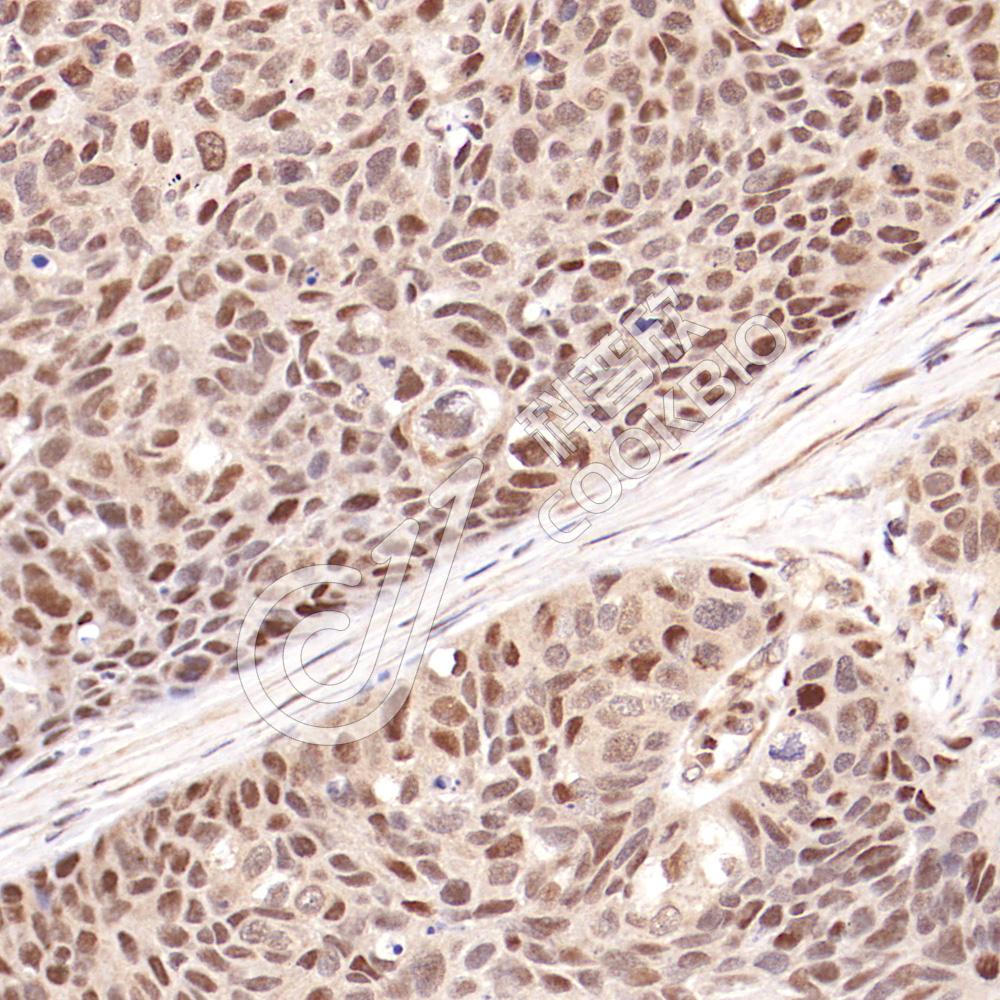

IHC检测Notch2蛋白(货号 K1341931).

样品: 人食管癌, 4%多聚甲醛 (货号KSG1101) 固定12-24小时.

抗原修复: 柠檬酸抗原修复液(干粉, pH 6.0) (KSG1201), 98℃, 20分钟.

—抗: 1: 900稀释, 4℃ 孵育过夜.

二抗: S-vision免疫组化多聚二抗(山羊抗兔),即用型 (货号KB3906), 室温孵育20分钟.